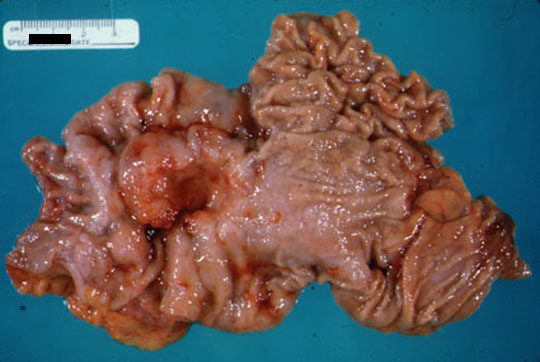

Cancer colon    The surgical specimen consisting of terminal ileum and proximal colon reveals a large, exophytic adenocarcinoma in the cecum.   Dr Ralph Leischner